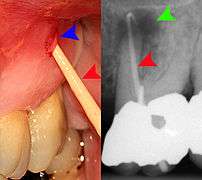

Clinical & xray correlation of pericoronitis

clinical shot of pericoronitis

An operculum (green arrow) over a partially erupted lower left third molar tooth. There is minimal inflammation and recurrent swelling.

xray of pericoronitis

A radiograph of the above tooth showing chronic pericoronitis, operculum (blue arrow) and bone destruction (red arrow) from chronic inflammation. Tooth is slightly disto-angular.

Pericoronitis is inflammation of the soft tissues surrounding the crown of a partially erupted tooth.[24] The lower wisdom tooth is the last tooth to erupt into the mouth, and is, therefore, more frequently impacted, or stuck, against the other teeth. This leaves the tooth partially erupted into the mouth, and there frequently is a flap of gum (an operculum), overlying the tooth. Bacteria and food debris accumulate beneath the operculum, which is an area that is difficult to keep clean because it is hidden and far back in the mouth. The opposing upper wisdom tooth also tends to have sharp cusps and over-erupt because it has no opposing tooth to bite into, and instead traumatizes the operculum further. Periodontitis and dental caries may develop on either the third or second molars, and chronic inflammation develops in the soft tissues. Chronic pericoronitis may not cause any pain, but an acute pericoronitis episode is often associated with pericoronal abscess formation. Typical signs and symptoms of a pericoronal abscess include severe, throbbing pain, which may radiate to adjacent areas in the head and neck,[20][25]:122 redness, swelling and tenderness of the gum over the tooth.[26]:220–222 There may be trismus (difficulty opening the mouth),[26]:220–222 facial swelling, and rubor (flushing) of the cheek that overlies the angle of the jaw.[20][25]:122 Persons typically develop pericoronitis in their late teens and early 20s,[27]:6 as this is the age that the wisdom teeth are erupting. Treatment for acute conditions includes cleaning the area under the operculum with an antiseptic solution, painkillers, and antibiotics if indicated. After the acute episode has been controlled, the definitive treatment is usually by tooth extraction or, less commonly, the soft tissue is removed (operculectomy). If the tooth is kept, good oral hygiene is required to keep the area free of debris to prevent recurrence of the infection.[20]:440–441